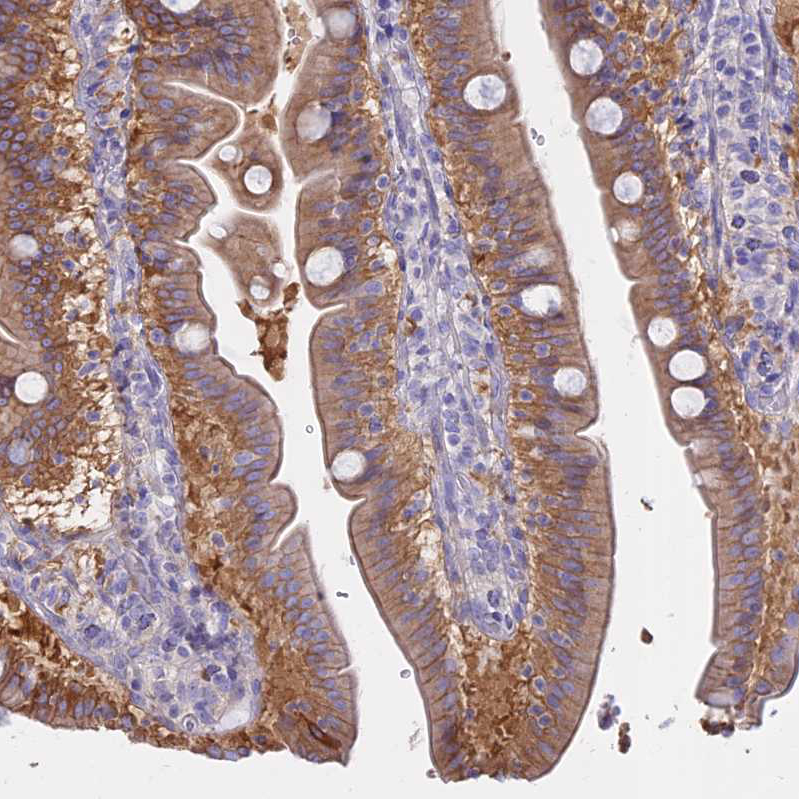

Immunohistochemical staining of human duodenum shows moderate membranous and cytoplasmic positivity in glandular cells.